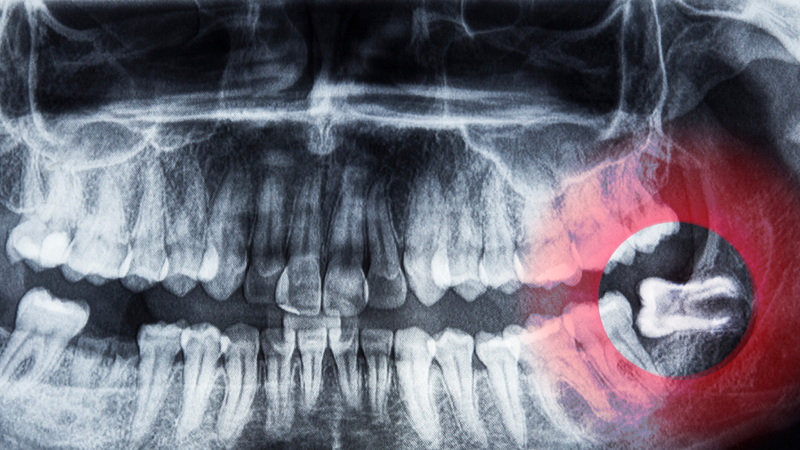

Chụp X-quang là một phương pháp quan trọng để xác định vị trí và hướng mọc của răng khôn. Qua hình ảnh X-quang, bác sĩ có thể thấy rõ răng khôn có bị kẹt, mọc lệch hay không, từ đó đưa ra phương án điều trị thích hợp. Thời điểm tốt nhất để chụp X-quang và kiểm tra răng khôn thường là khi bạn bắt đầu cảm thấy những triệu chứng đầu tiên, hoặc định kỳ mỗi 6 tháng nếu có tiền sử các vấn đề về răng khôn.

Răng khôn mọc có thể gây ảnh hưởng nghiêm trọng đến sự sắp xếp và vị trí của các răng khác trong hàm. Thường thì không gian trong hàm không đủ để răng khôn mọc lên một cách bình thường, dẫn đến việc chúng có thể mọc lệch, đâm ngang hoặc bị kẹt dưới lợi.

Khi răng khôn mọc lệch, chúng có thể gây áp lực lên các răng lân cận, làm dịch chuyển hoặc gây lệch lạc cho cả hàm răng. Điều này không chỉ ảnh hưởng đến thẩm mỹ mà còn gây khó khăn trong việc nhai và vệ sinh răng miệng. Trong một số trường hợp nghiêm trọng, việc răng khôn mọc không đúng cách có thể gây đau đớn và yêu cầu phải nhổ bỏ để tránh các biến chứng lâu dài.